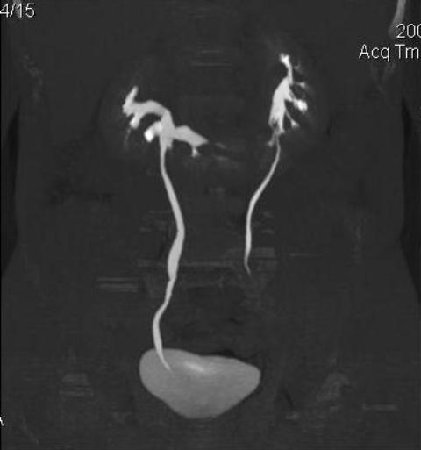

КТ Почек- подкова и уретеролитиаз

Ну ладно, раз никто больше не хочет, то отвечу свою версию - аномалия развития - подковообразная почка (horseshoe kidney).

Да красивая подковообразная почка - встречала раз 6-7.

Не вызывает сомнений. Картинка замечательная. Должно быть хорошо видно и на УЗИ.